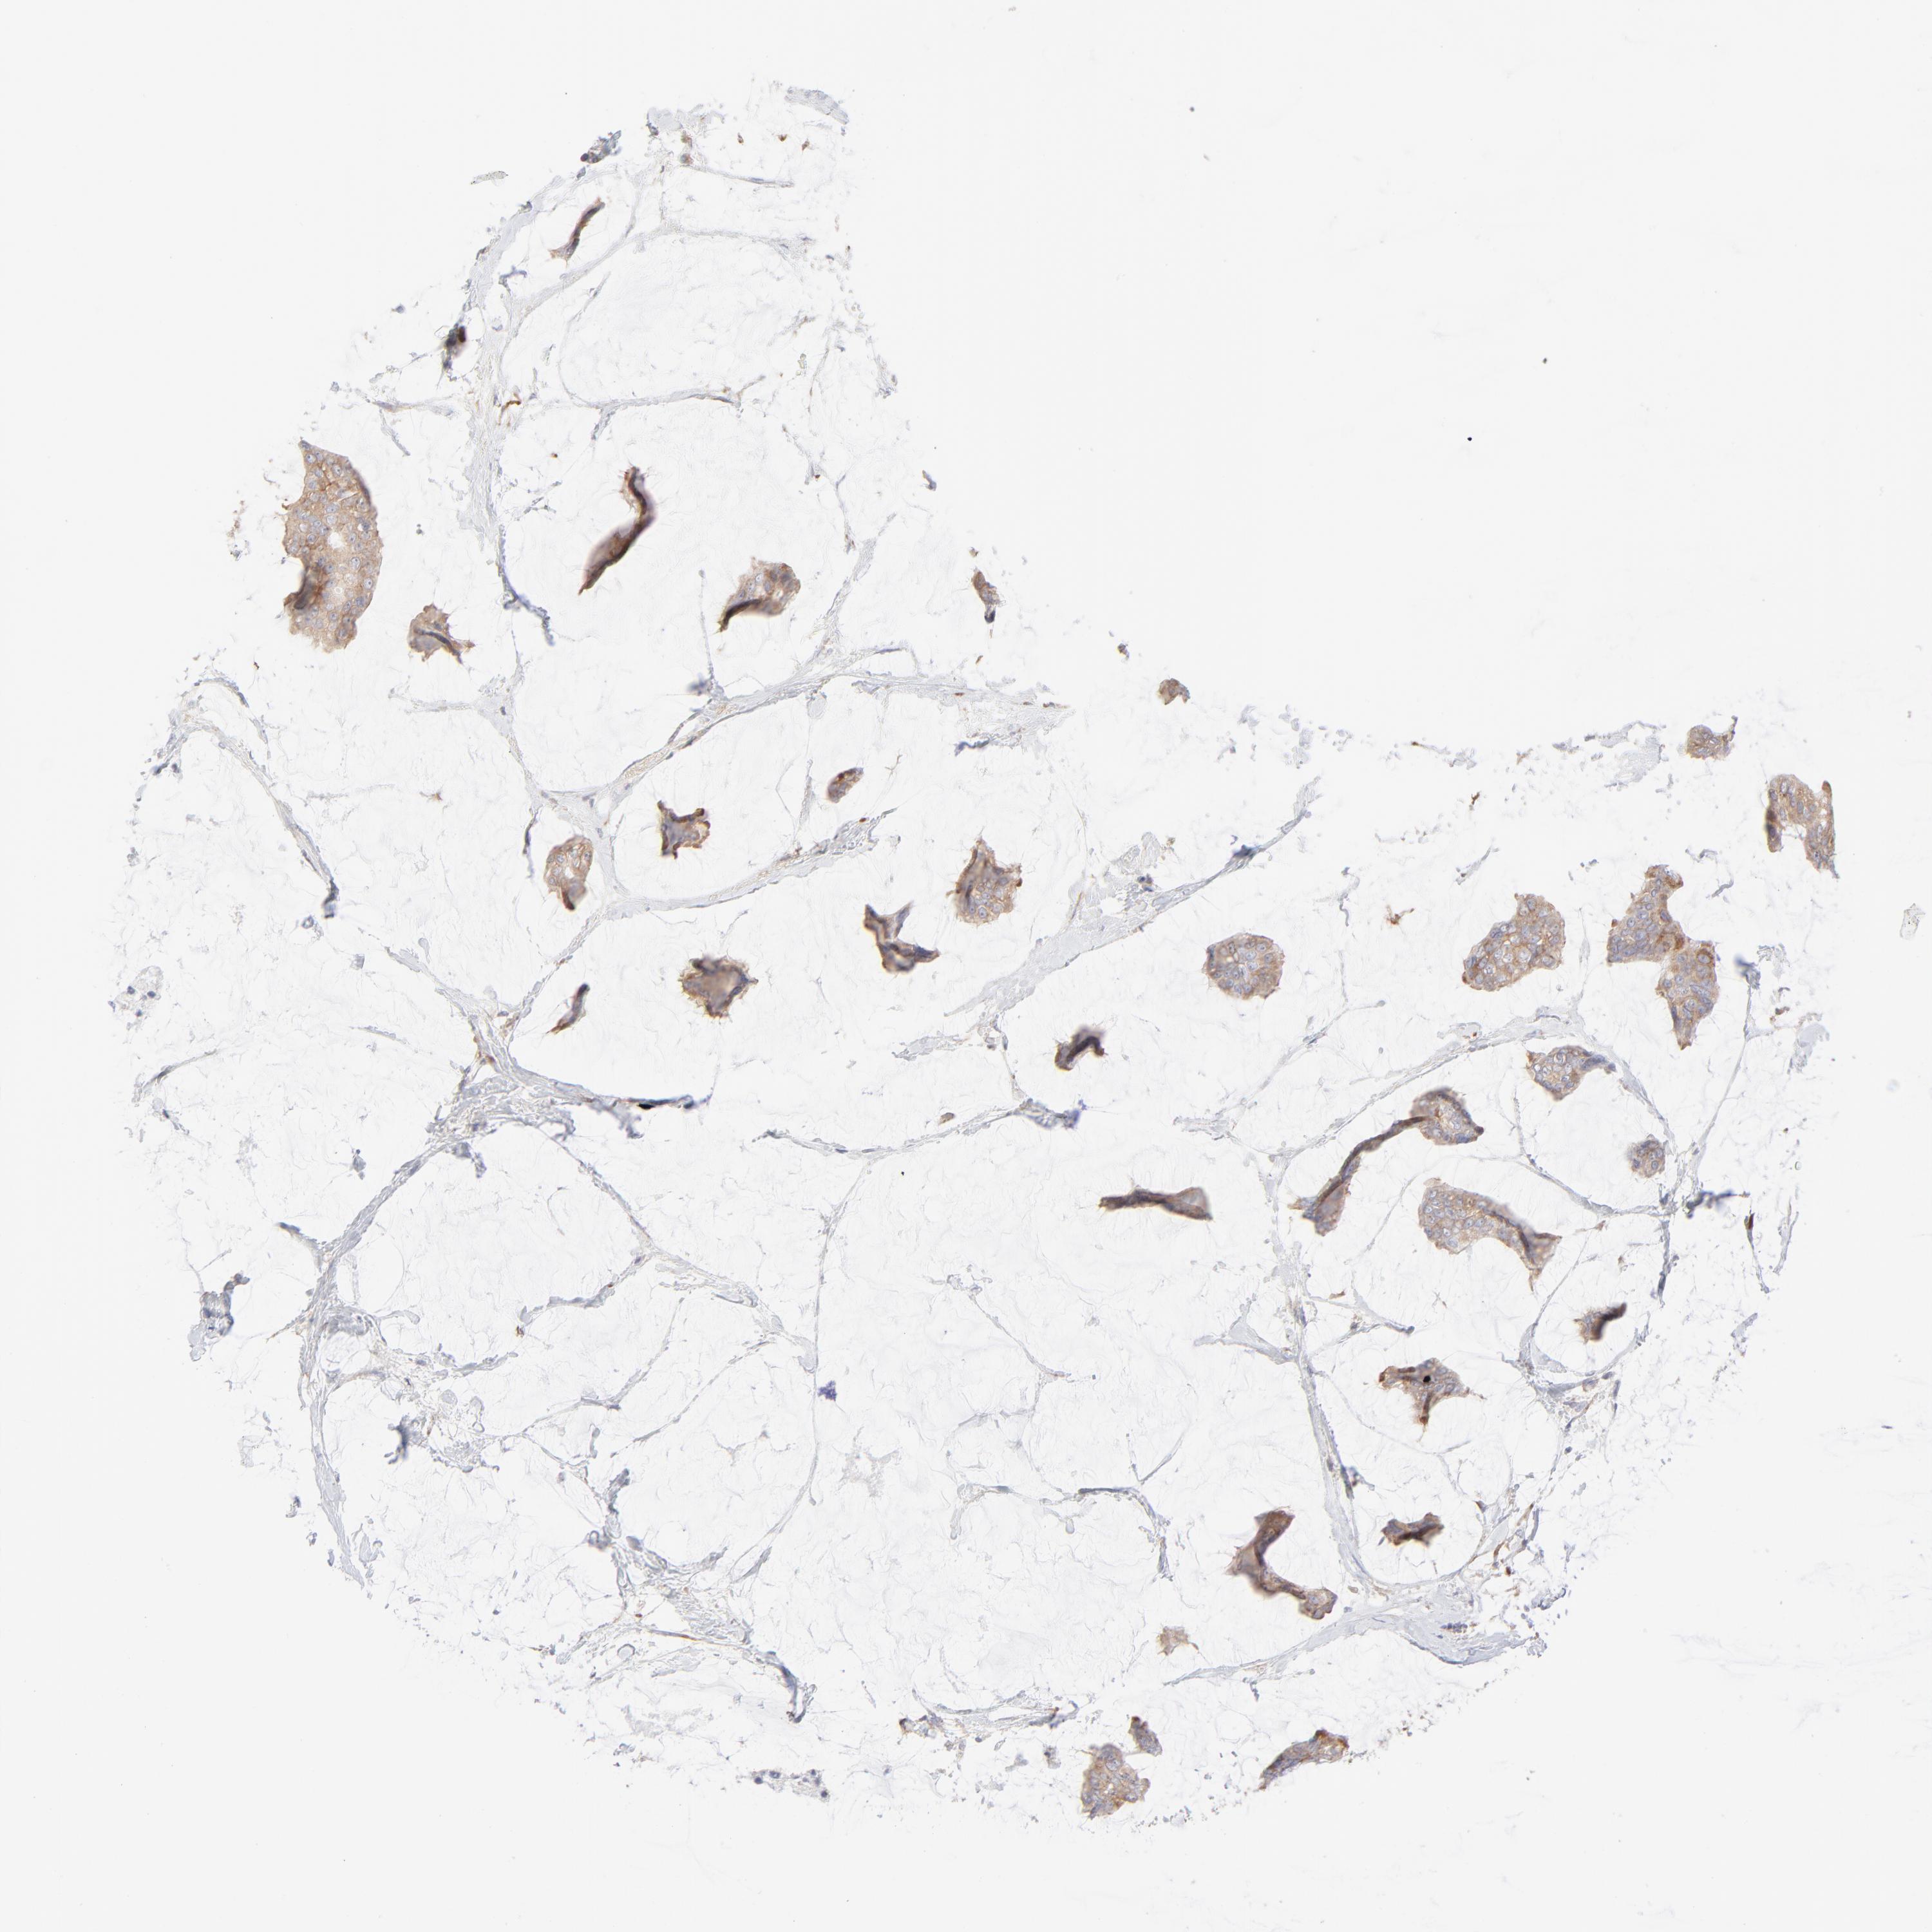

CANCER BREAST CANCER Show tissue menu

BRCA TCGA BRCA VALIDATION PROTEIN EXPRESSION

Breast cancer

Human cancer